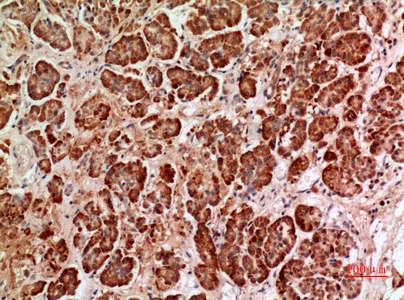

Histone deacetylase 9 Rabbit Polyclonal Antibody

Cat: APRab12050